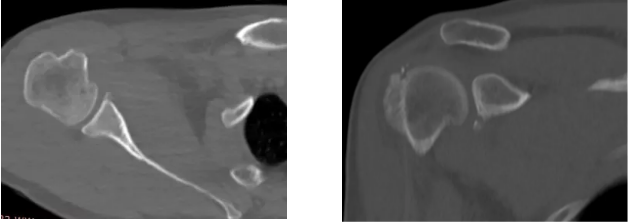

病例1

病史摘要:男性,44歲,跌傷致右肩關(guān)節(jié)疼痛數(shù)天,活動不利。

CT圖示:右側(cè)肱骨后外上方局部骨皮質(zhì)塌陷,連續(xù)性中斷(箭頭);肩胛盂前下份邊緣變鈍,見高密度分離小骨片影(三角形)。